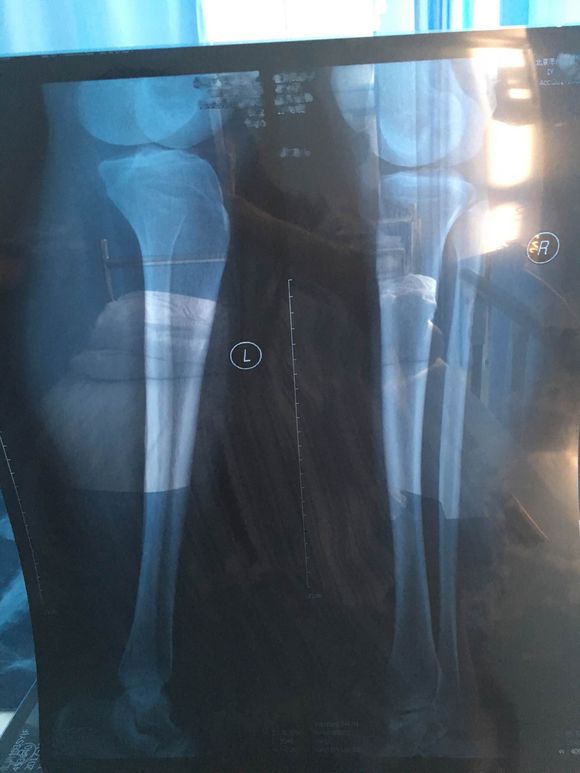

地方还是比较好找的,之前说好准备的X光片什么的我也都提前弄好了,去了医生看过之后做了详细的分析,说我这种情况除了膝内翻还有骨盆前倾的症状而且还比较严重,解释了一下治疗方法时候便开始进行治疗;进治疗室那一刻其实我还是蛮害怕的,医生和护士都在安抚我的情绪,让我不要紧张,打了麻药之后我脸就转过去了,害怕不敢看,整个手术持续了十几分钟,中间有微微的痛感,在护士的搀扶下我自己回到休息室等待麻药劲儿过去,之后进行力量训练,姿势训练,来恢复我不平衡的软组织。